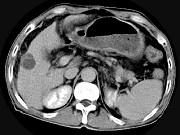

问题 男,63岁,肝区疼痛不适1个月,皮肤巩膜无黄染,AFP高于正常,CT所见如图,最可能的诊断是()

选项 A.肝血管瘤 B.肝转移瘤 C.阿米巴肝脓肿 D.不典型肝癌 E.胆管细胞癌

答案 D